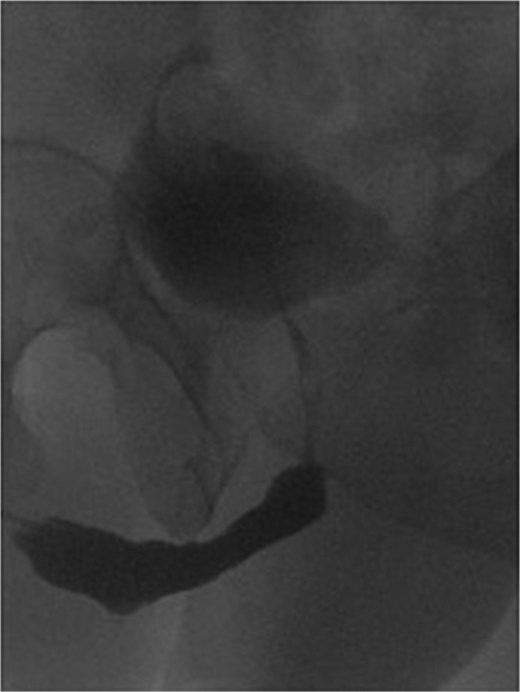

Physical examination revealed a soft and lax abdomen with a non-palpable bladder, and the urethral meatus was normally positioned without stenosis or blisters. A trial of urethrogram showed a pin-hole long segment urethra, limiting the quality of the study. Subsequently, a pelvic magnetic resonance imaging (MRI) was performed (Fig. 1), demonstrating attenuation of the prostatic urethral lumen with a low signal periurethral zone and faint high T2 signal in the membranous, bulbous, and penile urethra, supporting the diagnosis of pan-urethral stricture.

Sagittal MRI of the pelvis demonstrating a pan-urethral stricture. The urethra shows a long segment narrowing extending between the two arrows.